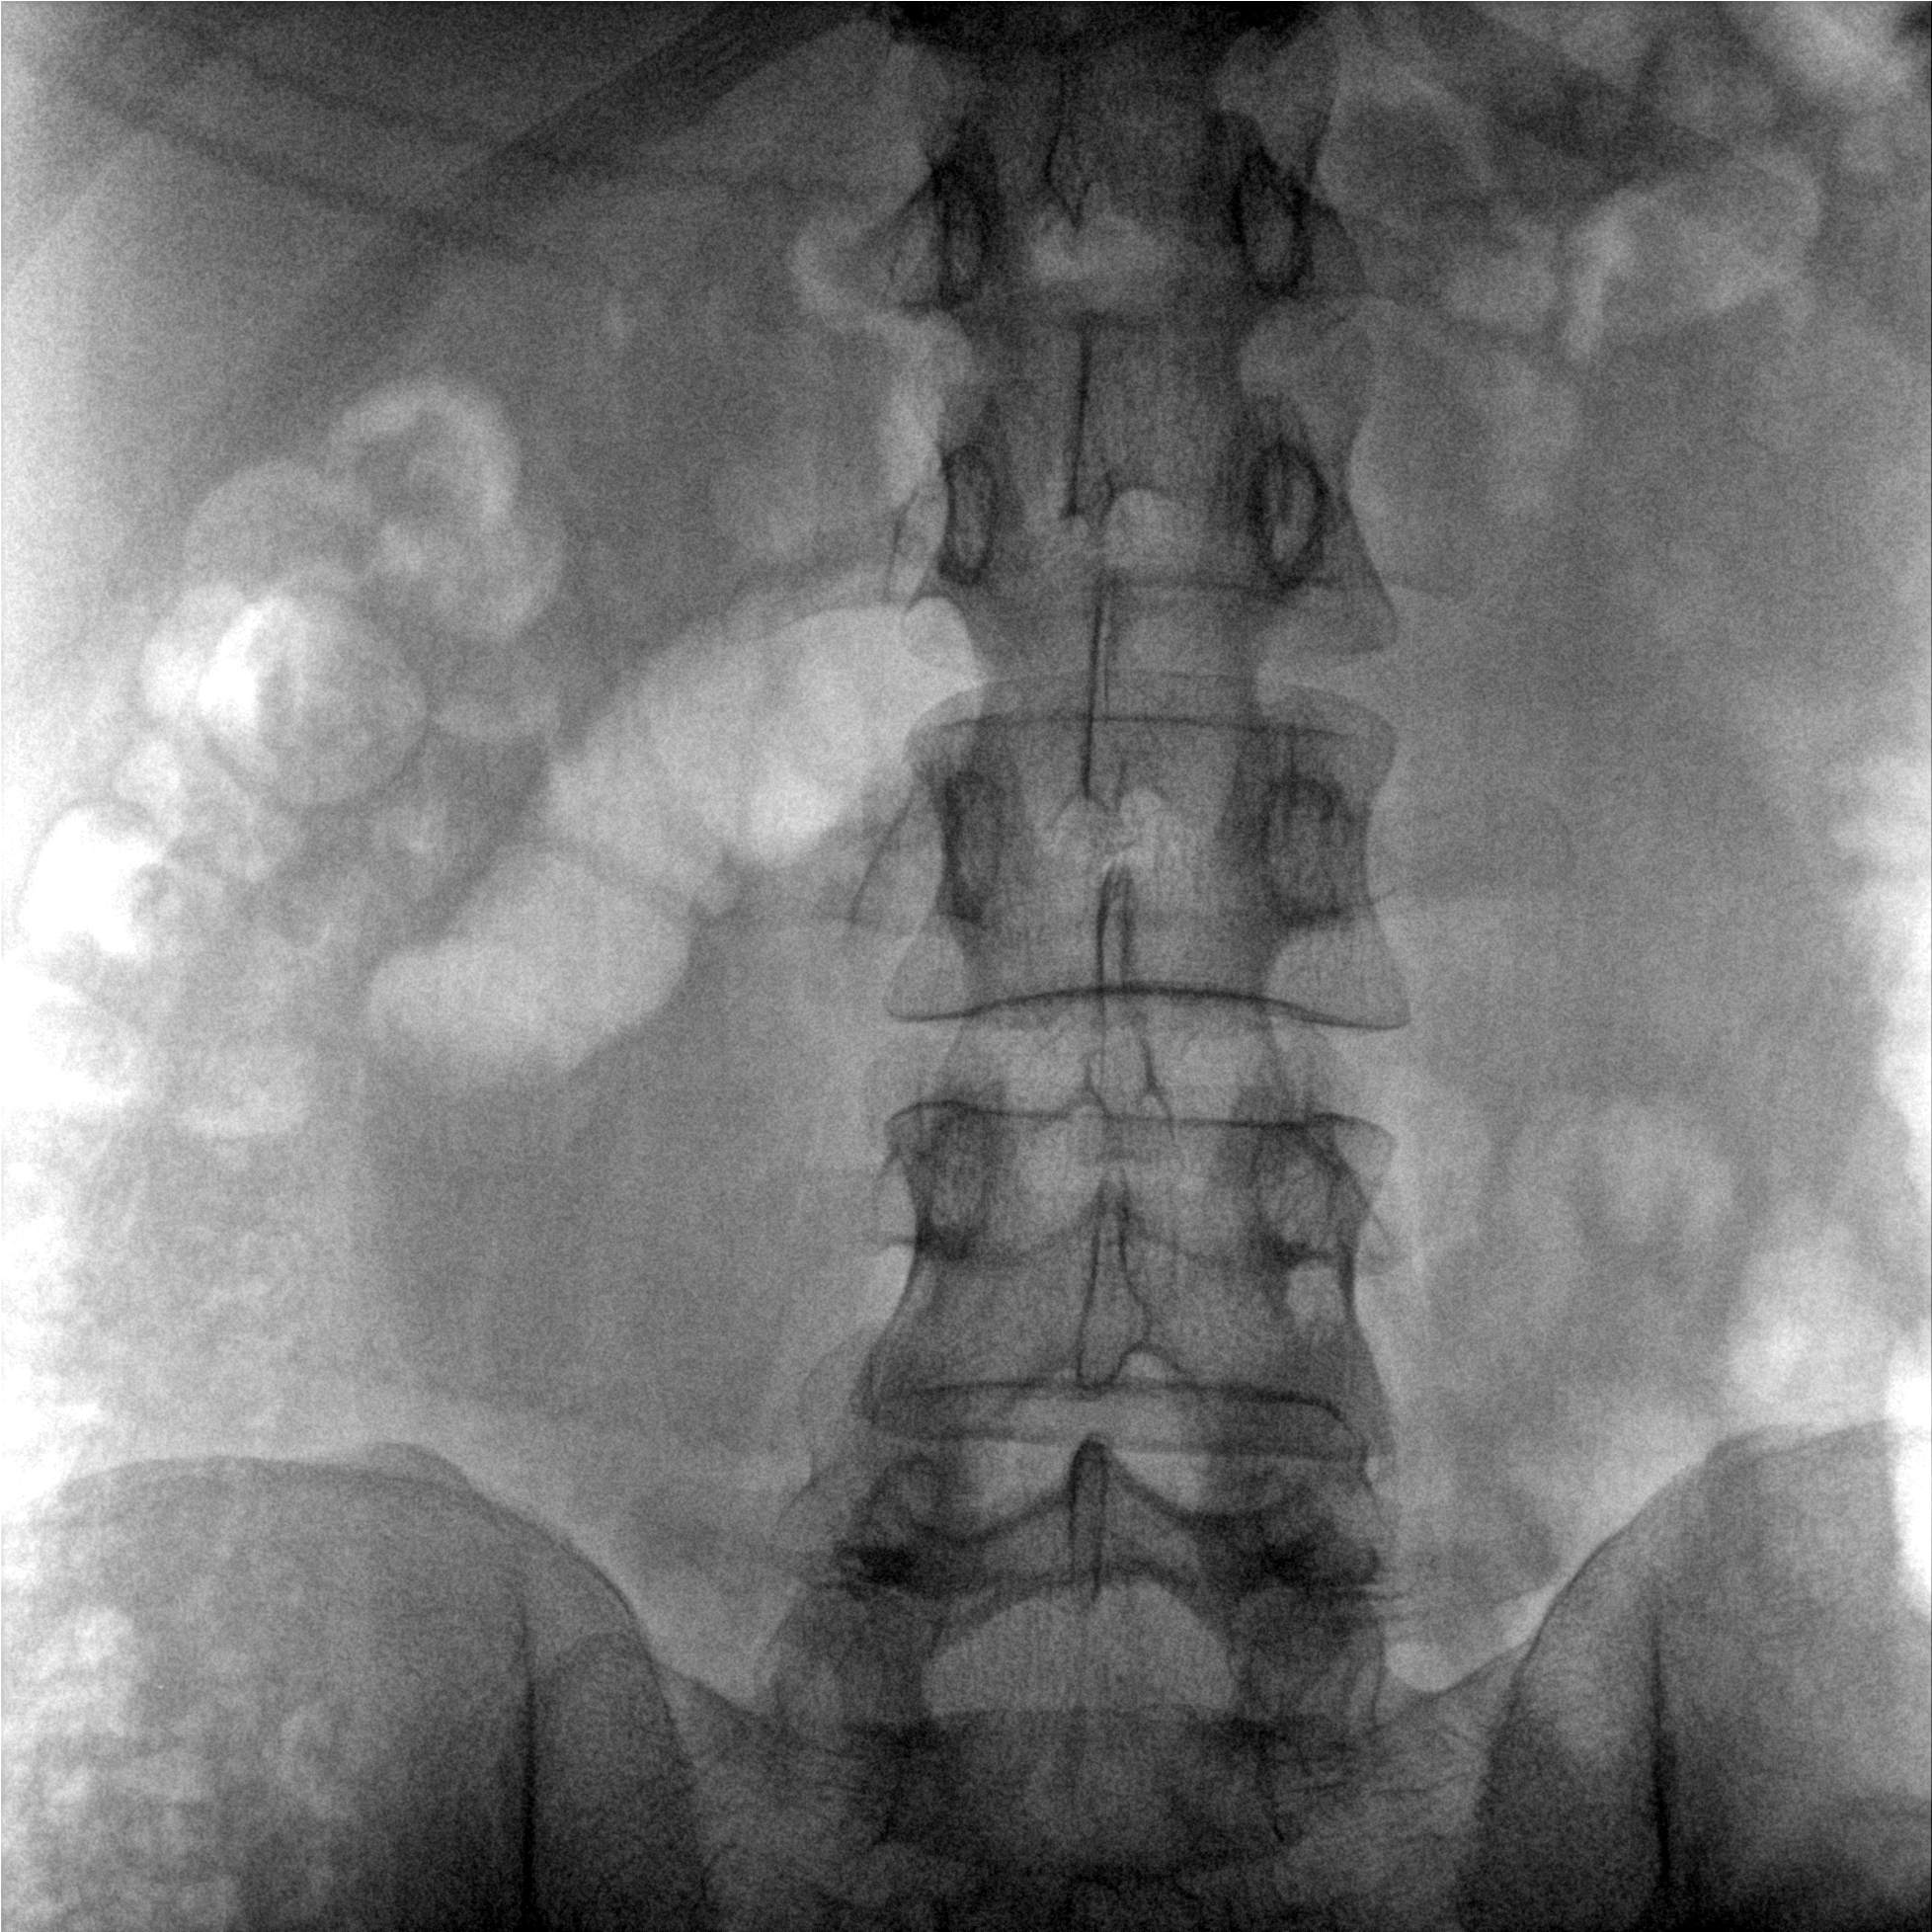

提供更大的术中三维成像视野,采集更多图像信息,可一次拍全全段颈椎、全段腰椎、七节胸椎、双侧骶髂关节、股骨头及单侧盆骨。